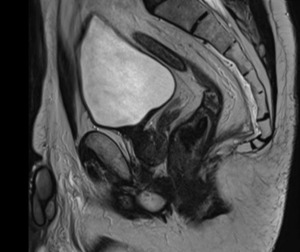

Inhomogeneous signal hyperintensity in T2-weighted sequences with a fluid/fluid level appearance, isointensity signal in T1-weighted sequences, no signal reduction in T1-weighted sequences in opposition of phase in agreement with the absence of a lipid component, no signs of signal restriction in diffusion (ADC 1.6), thin peripheral contrast enhancement, and thin septa in the structure were all features of the MRI. The lesion on the right posterolateral side appeared to affect the muscular coat, extending to the serosa raising suspicion for a teratomatous-type lesion. Following multidisciplinary consultation, surgical excision was planned. A transanal local excision was performed under general anesthesia (Figure 3). The patient’s postoperative course was uneventful, and he was discharged on the first postoperative day. Histopathological analysis revealed an edematous, ulcerated, and chronically inflamed segment of the large intestinal wall, containing lymphatic and intraparietal blood vessel ectasias consistent with hemolymphangioma. No postoperative complications were observed. The patient underwent regular follow-up evaluations, including proctological examinations, CT scans, and MRI studies (Figure 4) every six months for the initial two years, followed by annual assessments. At four years postoperatively, there is no evidence of disease recurrence.